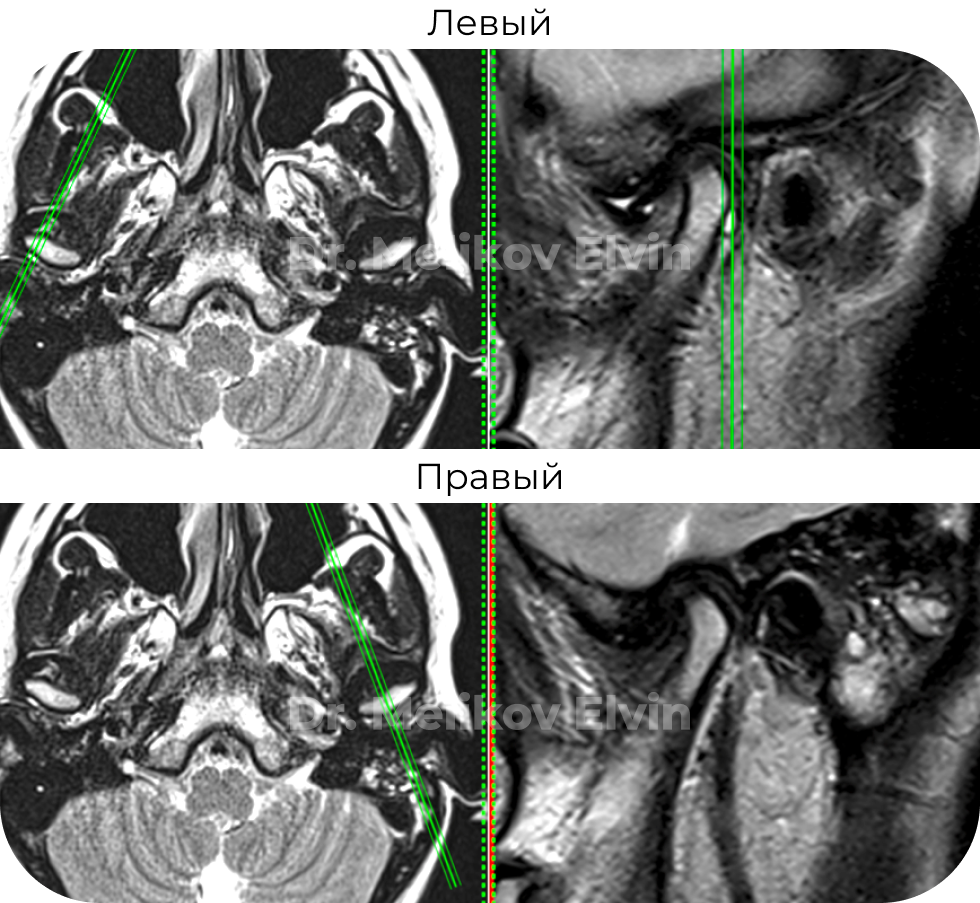

Магнитно-резонансная томография ДО лечения. Заключение:

МР-картина может соответствовать дисфункции височно-нижнечелюстного сустава, за счет частичной вентральной дислокации правого суставного диска с редукцией при открытии рта (подвывих), полной вентральной дислокации левого суставного диска без редукции при открытии рта (вывих).

Признаки артроза 2 степени ВНЧС справа и слева.